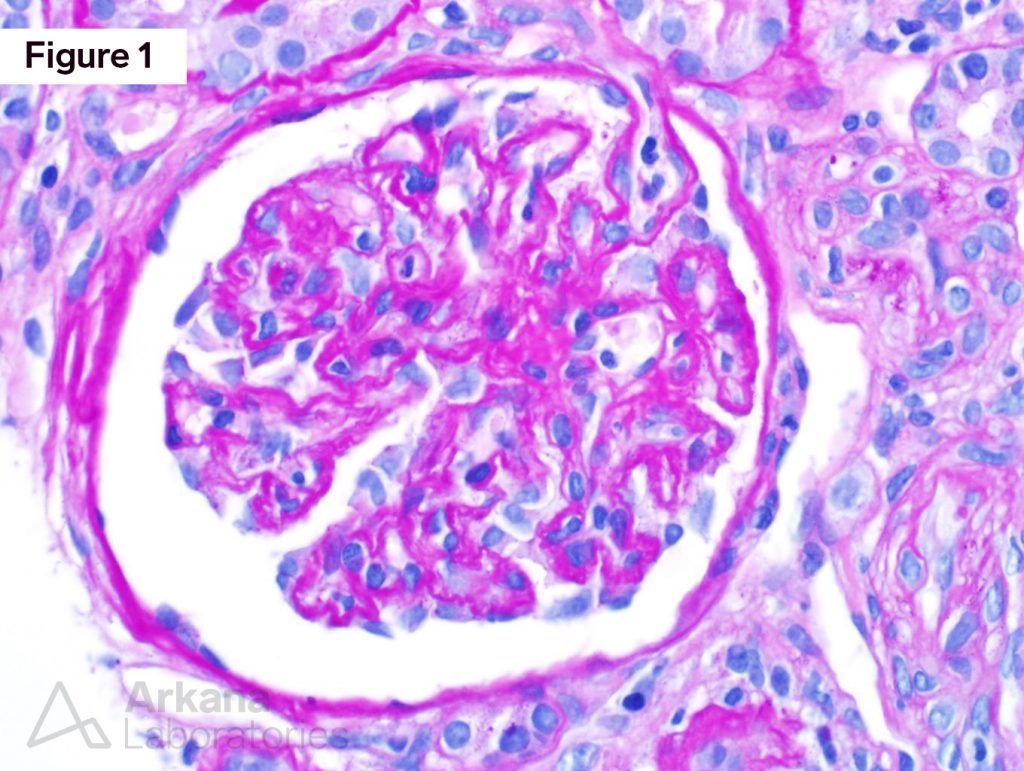

From www.arkanalabs.com

scleroderma renal crisis Archives Arkana Laboratories Onion Skin Kidney Histology There are intimal fibrosis with narrowed lumina and concentric. endothelial swelling and red blood cell fragments may be present in the arterial wall, and medial hypertrophy of small. The thickening has left a tiny lumen. renal histology revealed malignant nephrosclerosis, including an onion skin pattern with fibrinoid necrosis of the small arteries from. the cardinal morphological feature. Onion Skin Kidney Histology.